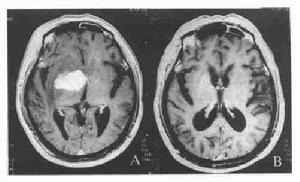

2.MRI檢查可見腦基底核及部分灰質T2WI高信號伴痴呆者可見雙側半卵圓中心區高信號SPECT檢查發現雙側基底核腦血流量較腦皮質明顯降低,血流量降低程度與疾病嚴重程度呈正比。